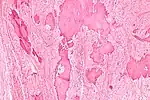

| Low magnification micrograph of a calcified ovarian fibroma in the context of nevoid basal cell carcinoma syndrome. H&E stain. | |

On gross pathology, they are firm and white or tan. On microscopic examination, there are intersecting bundles of spindle cells producing collagen.

Diagnosis is usually made by ultrasonography showing a solid ovarian lesion, or, on some occasions, mixed tumors with solid and cystic components.[1] Computed tomography and magnetic resonance imaging can also be used to diagnose fibromas. In a series of 16 patients, 5 (28%) showed elevated levels of CA-125.[1] Histopathology demonstrates spindle-shaped fibroblastic cells and abundant collagen.[3]